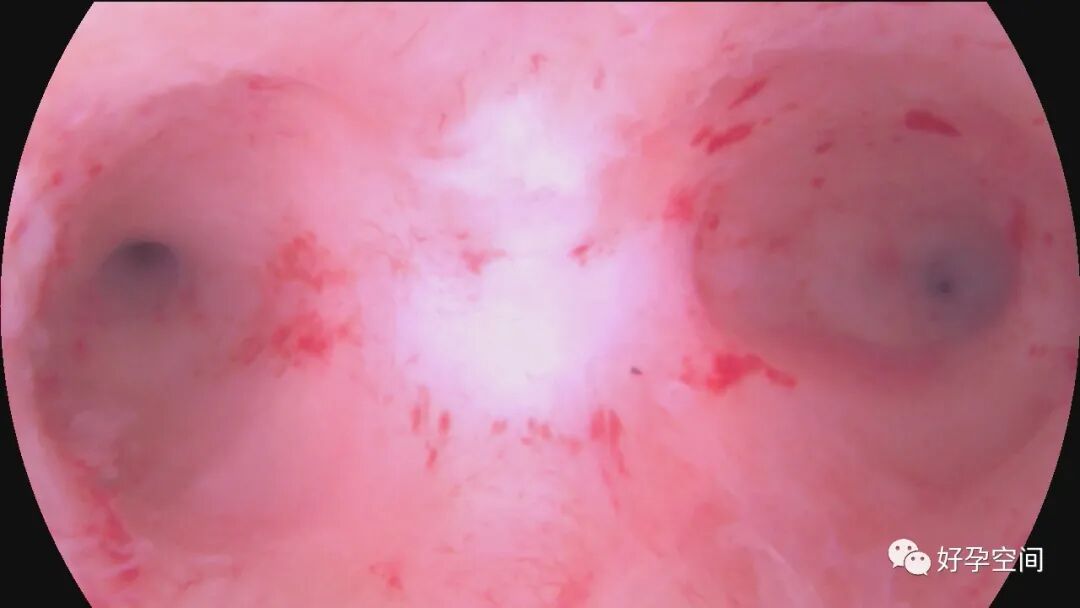

病例3:30岁,G3P1,顺产1次,孕12周胚胎停育1次并清宫,本次停经9+周,稽留流产。一次性宫腔镜见宫颈管下段息肉,约2.0*1.0*0.8cm,胚胎着床于宫腔下段后壁,不规则,张力差,摘除胚胎、切除息肉后见宫腔左侧粘连,切除粘连,宫腔形态正常,双侧输卵管开口可见。